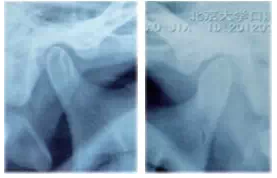

圖9雙側(cè)髁突在顳下頜關(guān)節(jié)窩內(nèi)的位置偏后上